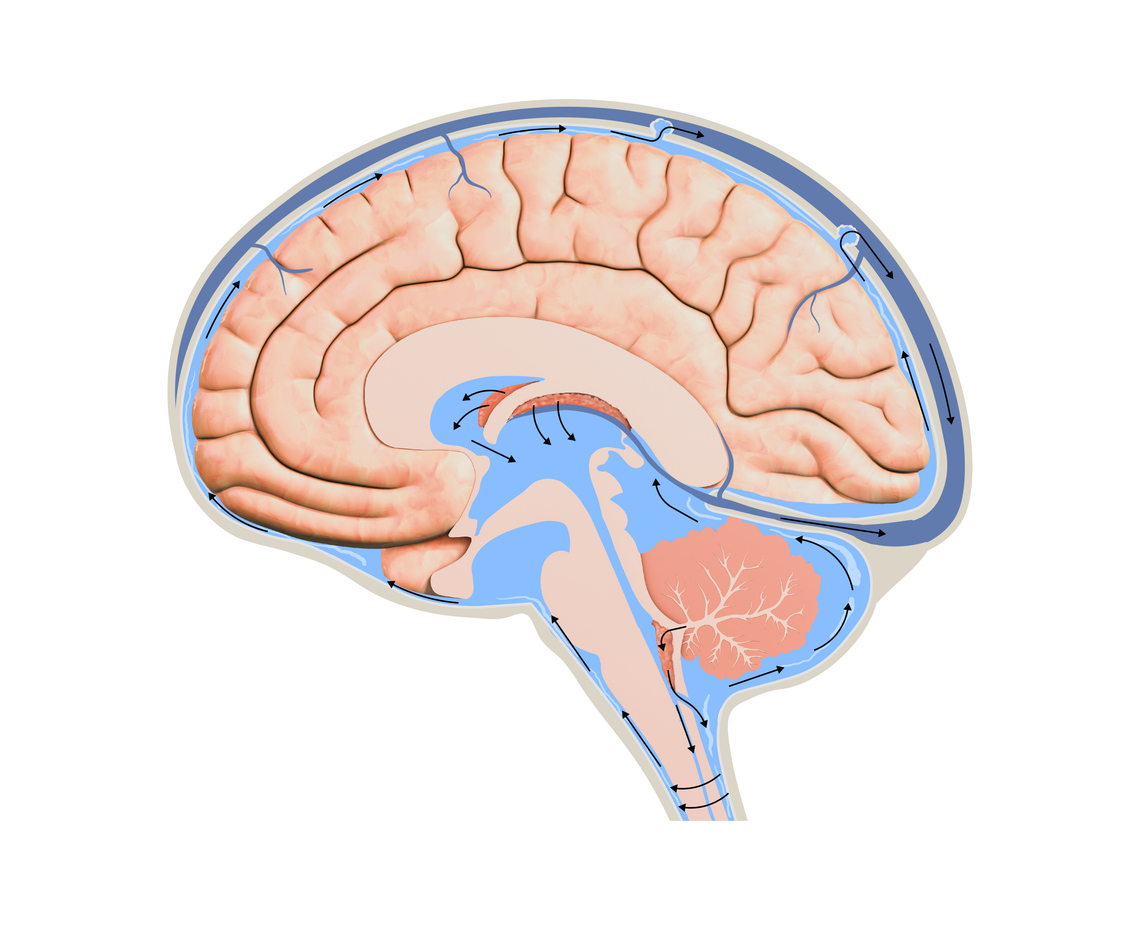

Waste Removal

Dr. Christopher Morrone is using his funding from Alzheimer’s Disease Research to study how a lack of sleep leads to protein buildup in the brain. Learn more.